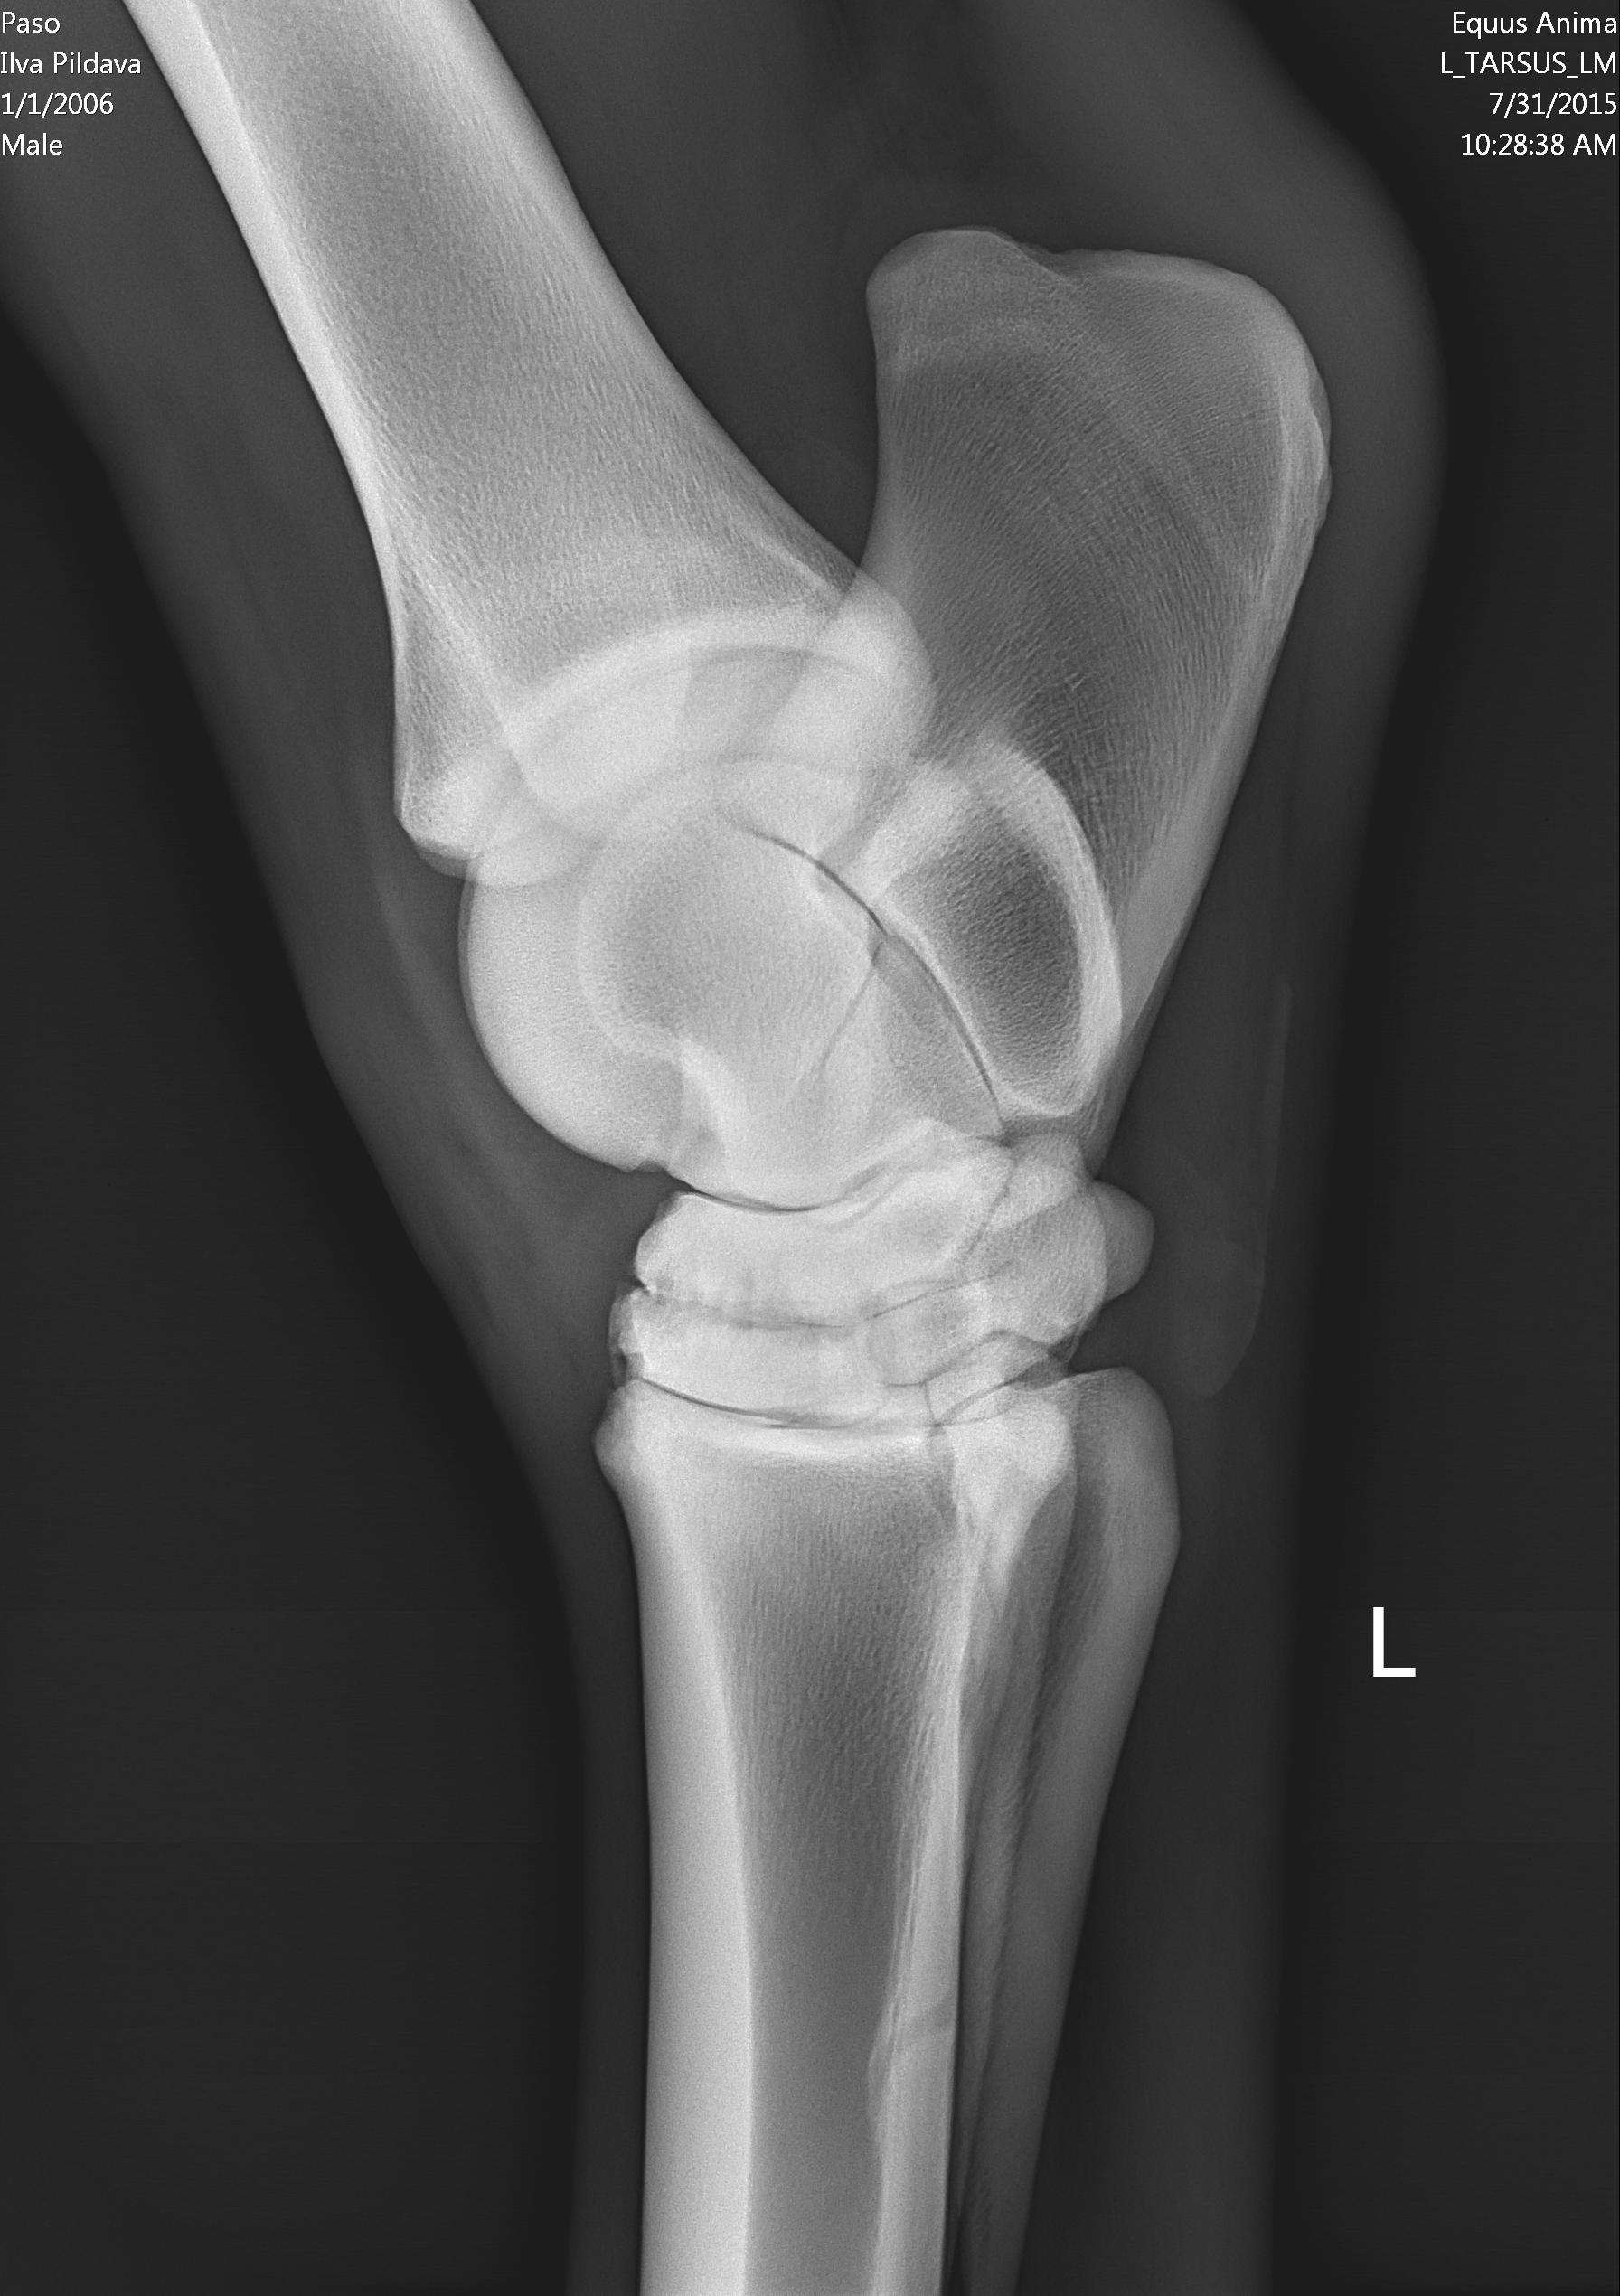

U majei loshadi ( 10 let) kastrat, v proslom godu obnaruzili spat I sdelali kurss Tildren, 16.10.2017. ehso odin kurss, daju polgoda eto http://ru.eggersmann.info/432_/132_Profi_Gelenk_aktiv.html, I vot kakije u loshadi rentgeni po datam. Prigaju do 110 cm, edu na sorevnavanije, idjot on horosho. esli stojal v bokse , snachala hromaet,no potom 2-4 minuti v risi i prohodit. Ja bi hotela prigatj vishe,no bojus ,mozno li. Letom dva raza bila ,chto v trenirovke zahramal ochen silno,no cerez paru chasov ,vsjo proslo.